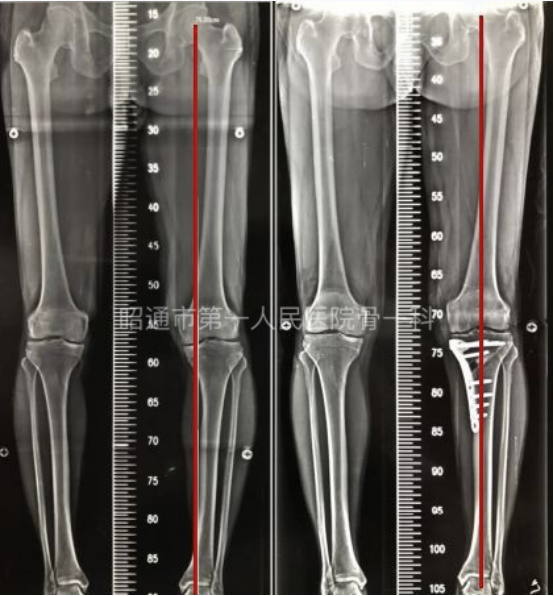

(术前及术后下肢力线评估)